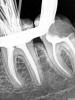

Magdalena Опубликовано 2 декабря, 2012 Поделиться Опубликовано 2 декабря, 2012 (изменено) Пациентка 28 л, обратилась с жалобой на скол стенки зуба 3.6. Объективно: зуб под обширной пломбой с нарушением прилегания, кариозная полость на дистальной поверхности. Перкуссия, пальпация безболезненныНа снимке увидела ступень, сразу предупредила о ее наличии, а также, что в процессе лечения может быть перфорация. В 1ое посещение прошла дистальный щечный и медиальный язычный, ступень в медиальном щечном не прошла, постоянно втыкалась в нее. Работала не в своем кабинете, скопа под рукой не былоОтправила на КТ, давайте, говорю, посмотрим, есть там дальше ход или нет (хотя, конечно, уверена была, что есть). На КТ четко видно, что медиальные проходимы до апекса. Во 2ое посещение, опять воткнулась в ступень, глянула в скоп и увидела кусок гутты в просвете канала, хотя на снимке с инструментами материала в канале не видно. Гутту убрала, канал прошла.Обработка 3,25% р-р гипохлорита, УЗ, в конце обработки - дист. вода и 17% ЭДТА, mtwo до 25\06, доработка ручными в медиальных до № 30, в дистальном № 45, все остальные пролетали. Смущает, что такой широкий дистальный, не расширяла специально, mtwo только по стенкам поскребла, все остальное УЗ. 2ого дистального точно нет, не в скоп, ни по КТ. Изменено 2 декабря, 2012 пользователем Magdalena 4 Ссылка на комментарий